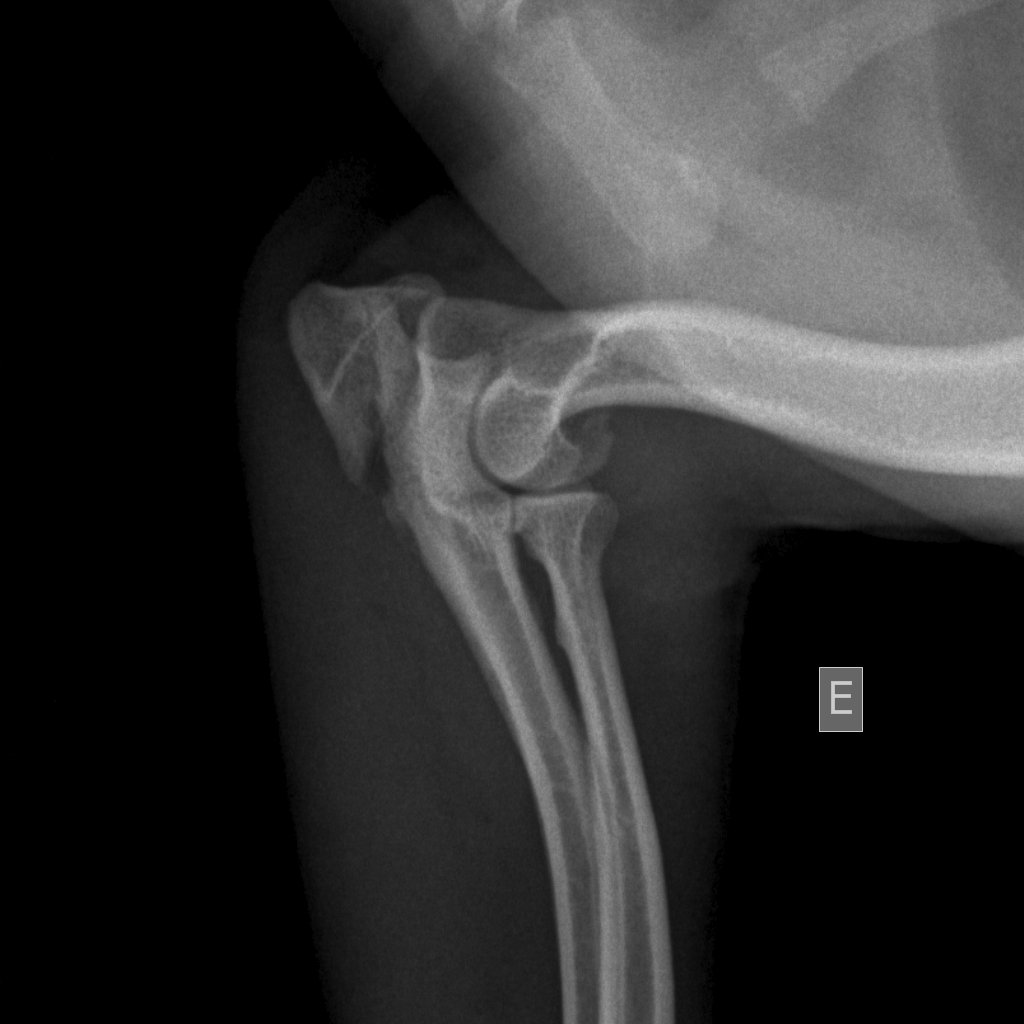

HistÛria a Maia foi atropelada dia 27 de julho de 2010. Ficou com o membro anterior esquerdo todo esmagado, desde o cotovelo atÈ aos dedos. | DiagnÛstico fractura do carpo e metacarpo, fractura do olecr‚neo.Sizalamento do carpo e metacarpo esq e dedo 5 MAETratamento reduÁ„o da fractura do olecr‚neo com bandas de tens„o. AmputaÁ„o do dedo lateral desvitalizado. Sutura dos tecidos moles |